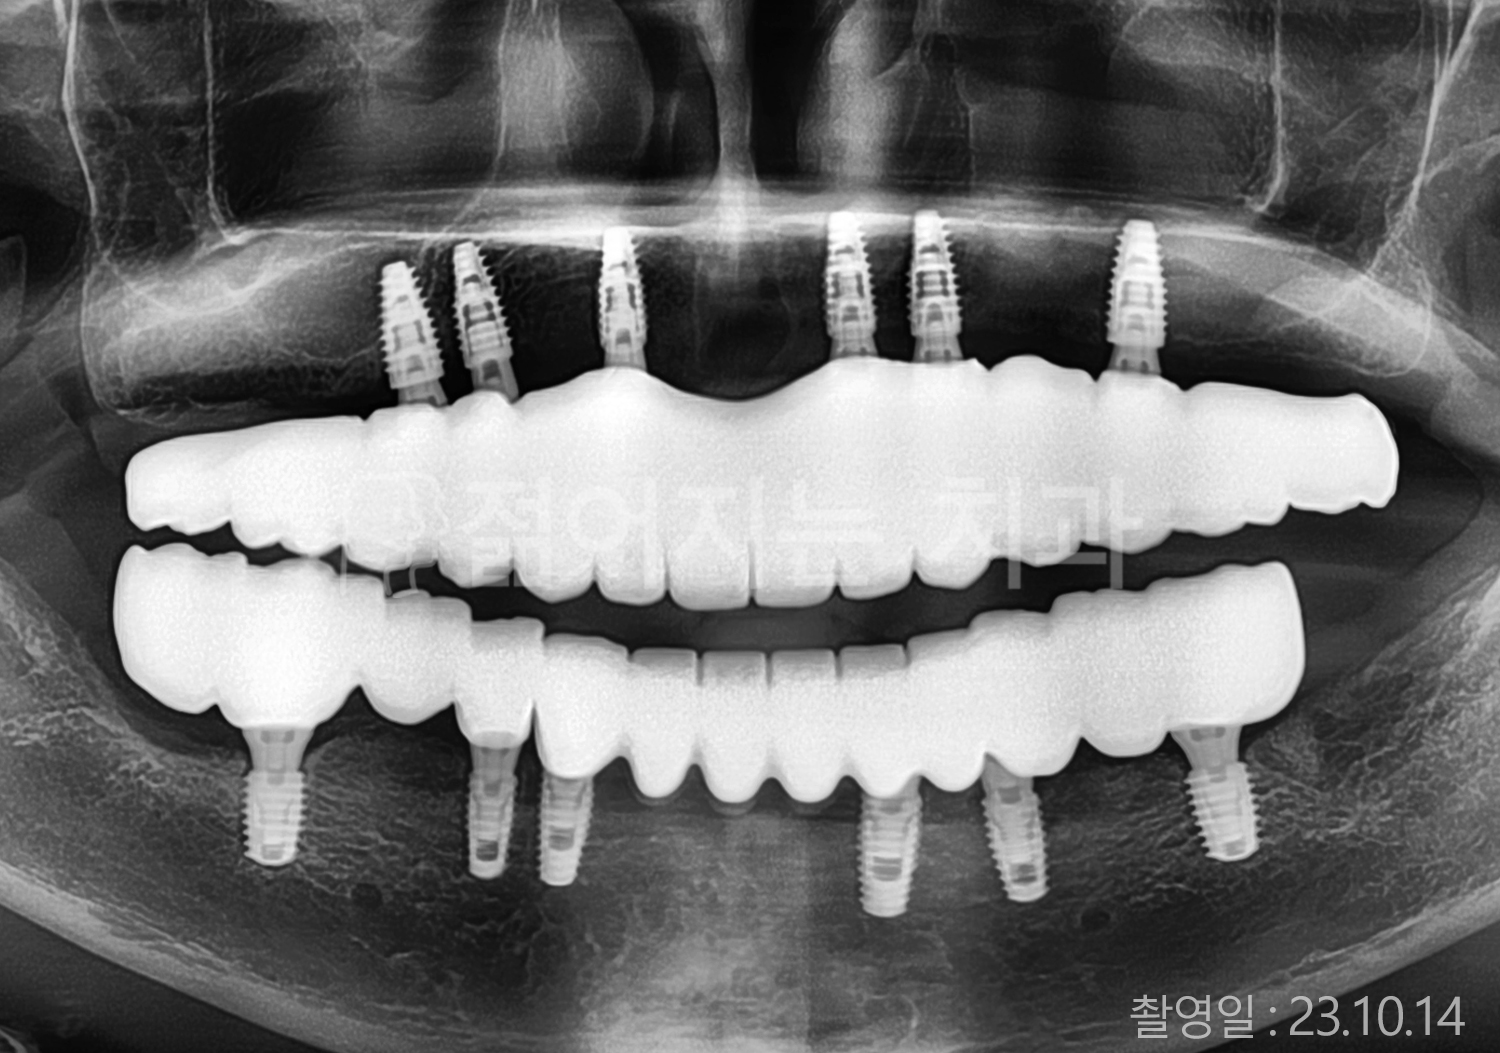

• 50대 고혈압, 당뇨, 고지혈증 전체치아 10개 이상 임플란트

• 60대 골다골증, 간경화 전체치아 10개 이상 임플란트

• 60대 고혈압, 고지혈증 전체치아 10개 이상 임플란트

• 50대 고혈압, 당뇨 전체치아 10개 이상 임플란트

• 60대 고혈압 전체치아 10개 이상 임플란트

• 60대 전체치아 10개 이상 임플란트

• 60대 고지혈증 전체치아 10개 이상 임플란트

• 40대 전체치아 10개 이상 임플란트

• 70대 전체치아 10개 이상 임플란트